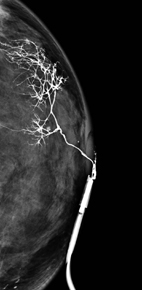

乳管攝影(ductography or galactography)對於引起乳頭分泌物的乳管內病灶具有極佳的影像解析度,這是一種侵入性的影像學檢查,首先是經由乳頭流出分泌物的乳管開口放置一支極細的乳管針(30-gauge,約0.31mm口徑)進入乳管內,然後由乳管針注射大約0.1-0.3 cc 的水溶性含碘對比劑,然後針對該乳房照X光攝影,含碘對比劑可以將正常乳管的內部情形清晰的呈現出來 (圖一),能清楚地顯示乳管是否有乳管擴張症,乳管內是否有微小的腫瘤 (圖二箭頭處),以及腫瘤的形狀、數量、位置及其距離乳頭之深度,提供正確的診斷,有助正確的治療方式。根據國外醫學研究,乳管攝影對於偵測引起乳頭分泌物的乳管病灶,其敏感度可達77-86%,準確度達80%,若是搭配3D乳房斷層攝影(digital breast tomosynthesis, DBT)的技術,此即3D斷層乳管攝影(DBT-ductography),其敏感度更高達95%,準確度高達96%。

圖一、正常乳管